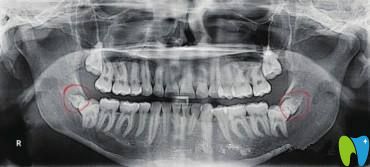

很多人反映,在拍口腔CT的時(shí)候發(fā)現(xiàn)了阻生牙,并且是智齒,醫(yī)生建議拔除,但是不檢查也不會(huì)發(fā)現(xiàn)牙齒有什么問題啊,那么阻生牙和智齒一樣嗎?阻生牙沒有什么不適癥狀也需要拔除嗎?

牙齒在頜骨內(nèi)由于位置不正,不能萌出到正常的咬合位置,這樣的牙齒稱為阻生牙。常見的阻生齒是下頜第三磨牙(智齒),其次是上頜第三磨牙(智齒)和上頜尖牙。所以阻生牙不一定是智齒,也可能是其它牙齒,如果智齒萌出正常,則不能稱為阻生牙。